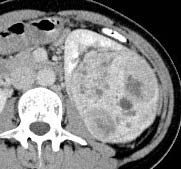

But, when we analyzed the degree of enhancement (hyperdensity, isodensity, hypodensity) in arterial (corticomedullary) and venous (nephrographic) phases showed significant difference. In arterial phase, most of clear cell RCC (21 of 39, 53.8%) showed hyperdensity, whereas none of non -ccRCC (0 of 22,0%) showed hyperdensity. The P value was 0 (P<0.05). In venous phase, ccRCC showed more hyperdensity or isodensity (9 and 4 0f 39, 23.1% and 10.3% respectively) than non-ccRCC (0 and 1 of 22, 0% and 4.5% respectively). Almost all of the non-clear cell RCC ( 21 However, we did not get any significant difference, when compared degree of enhancement in delayed phase (excretory phase). Table 3: shows the comparison of degree of enhancement in different phases in between ccRCC and non-ccRCC. The pattern of enhancement (homogeneous or heterogeneous) showed significant difference. Nonclear cell carcinoma (19 of 22, 86%) showed more heterogeneous enhancement pattern than that of clear cell carcinoma (21 of 39,53%). The P value was 0.012 (p<0.05).

Now-a-days, the incidence of renal cell carcinoma is increasing due to increasing risk factors (obesity, smoking) and utilization of modern imaging techniques [11][12][13]29]. A majority of renal tumors are incidentally diagnosed on medical imaging, that's why most of them are asymptomatic, small in size and present at an earlier stage [14,27]. It is important to discriminate clear cell RCC from non-clear cell RCC because of ccRCC is generally considered to have a worse prognosis and is treated differently than other subtypes [15][16][17][18]27]. Several study has been done previously to differentiate clear cell RCC from non-clear cell RCC by using imaging modalities. The most consistent finding was that, degree of enhancement was the most valuable parameter for differentiation of renal cell carcinoma subtypes. Clear cell RCC S enhance to a greater degree than other subtypes of malignant lesions [8,10,[19][20][21][22]. Some researchers stated that the strong enhancement of conventional renal carcinoma is caused by it , s rich vascularity and alveolar architecture at histologic examination [4,10,23]. Our study consistent with these study. In this study, we found ccRCC (53.8%) showed more hyperdensity than that of non-ccRCC(0%). Most of non-ccRCC (95.5%) had hypodensity in all phases.